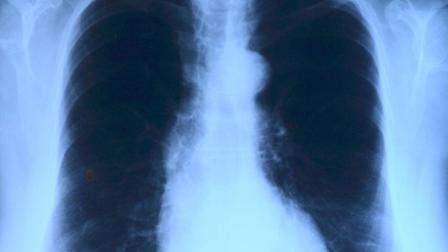

Hay que entender en primer lugar que el tabaco por definición no es bueno. Pero es importante que pensemos también que no sólo es malo para los pulmones sino que a su vez está relacionado con los infartos y con el cáncer, y hay más 'dianas' que no tenemos en cuenta.

A su vez, resalta que enfermedades como el asma se agrava con el tabaco y el tabaco favorece la Enfermedad Pulmonar Obstructiva Crónica o EPOC, una enfermedad "muy incapacitante", en la que los bronquios se obstruyen y el pulmón se destruye como consecuencia de aspirar el humo del tabaco y de otras sustancias, y con "una calidad de vida pésima" para quien la padece, siendo necesaria la oxigenoterapia constantemente.